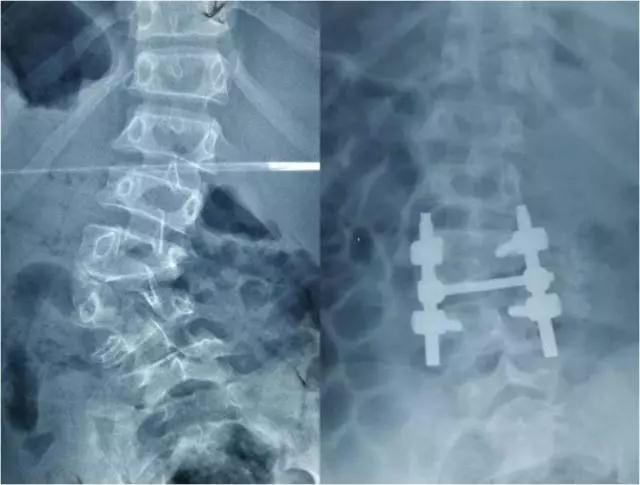

农忙之后,尼珍的妈妈带她到门诊照了X线片,结果发现,尼珍的腰椎第3节只发育了一半。这在医学上称为“腰椎半椎体畸形”,也就是说尼珍腰椎第3节只有左侧的一半,右侧没有。左侧的半椎体逐渐生长,导致尼珍出现了脊柱侧弯,肩膀倾斜。小尼珍才11岁,随着长大,她的脊柱会越来越弯,她的肩膀会越来倾斜……

手术历时5个小时,半椎体切除后,侧弯得到了很好的矫正。

术前和术后腰椎X线